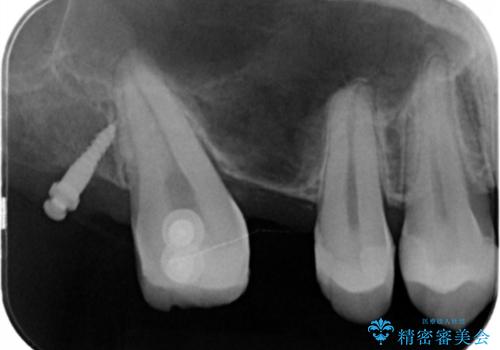

なので親知らずを抜歯して、一番奥の歯を部分矯正(upライト)をして倒れ込んでいる歯を起こしてスペースを作り、ブリッジの治療を行いました。

適合の良いブリッジが入りました。

歯の傾きを改善することにより食べ物が詰まりにくくなりました。